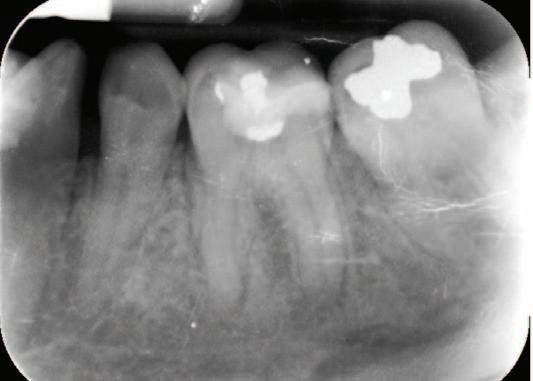

FIGURE 2: Left: Periapical radiograph pre endodontic treatment. Right: Post-endodontic treatment radiograph showing the presence of root canal filling material (AH Plus) inside the inferior alveolar canal.

Radiographic examinations consisted of digital orthopantomogram (OPG), peri-apical (PA), and cone beam computed tomography (CBCT) scans. The scans revealed that the lower left first molar root canals were obturated with a radiopaque material, and showed root canal filling extending beyond the apices of the tooth and approximately 5cm along the mandibular canal ( Figures 1 , 2 and 3 ).